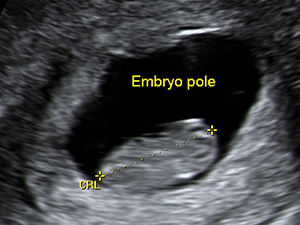

The crown-rump length of the embryo at 9 weeks